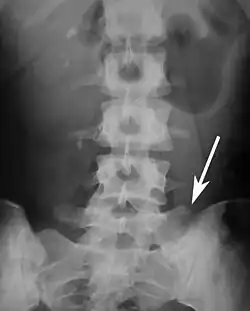

Lumbarization of sacral vertebra 1, seen as 6 vertebrae that do not connect to ribs.

Lumbarization is an anomaly in the spine. It is defined by the nonfusion of the first and second segments of the sacrum. The lumbar spine subsequently appears to have six vertebrae or segments, not five. This sixth lumbar vertebra is known as a transitional vertebra. Conversely the sacrum appears to have only four segments instead of its designated five segments. Lumbosacral transitional vertebrae consist of the process of the last lumbar vertebra fusing with the first sacral segment. [1] While only around 10 percent of adults have a spinal abnormality due to genetics, a sixth lumbar vertebra is one of the more common abnormalities. [2]